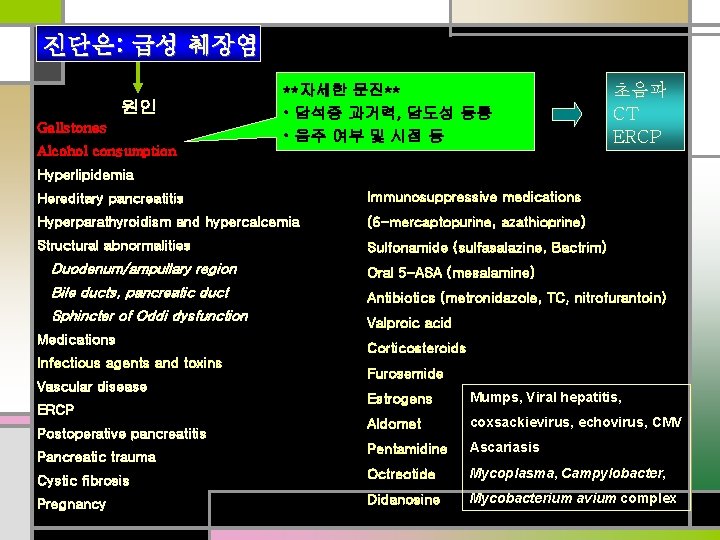

진단은: 급성 췌장염 원인 Gallstones **자세한 문진** • 담석증 과거력, 담도성 동통 • 음주 여부 및 시점 등 Alcohol consumption 초음파 CT ERCP Hyperlipidemia Hereditary pancreatitis Immunosuppressive medications Hyperparathyroidism and hypercalcemia (6 -mercaptopurine, azathioprine) Structural abnormalities Sulfonamide (sulfasalazine, Bactrim) Duodenum/ampullary region Oral 5 -ASA (mesalamine) Bile ducts, pancreatic duct Antibiotics (metronidazole, TC, nitrofurantoin) Sphincter of Oddi dysfunction Medications Infectious agents and toxins Vascular disease Valproic acid Corticosteroids Furosemide Estrogens Mumps, Viral hepatitis, Aldomet coxsackievirus, echovirus, CMV Pentamidine Ascariasis Cystic fibrosis Octreotide Mycoplasma, Campylobacter, Pregnancy Didanosine Mycobacterium avium complex ERCP Postoperative pancreatitis Pancreatic trauma